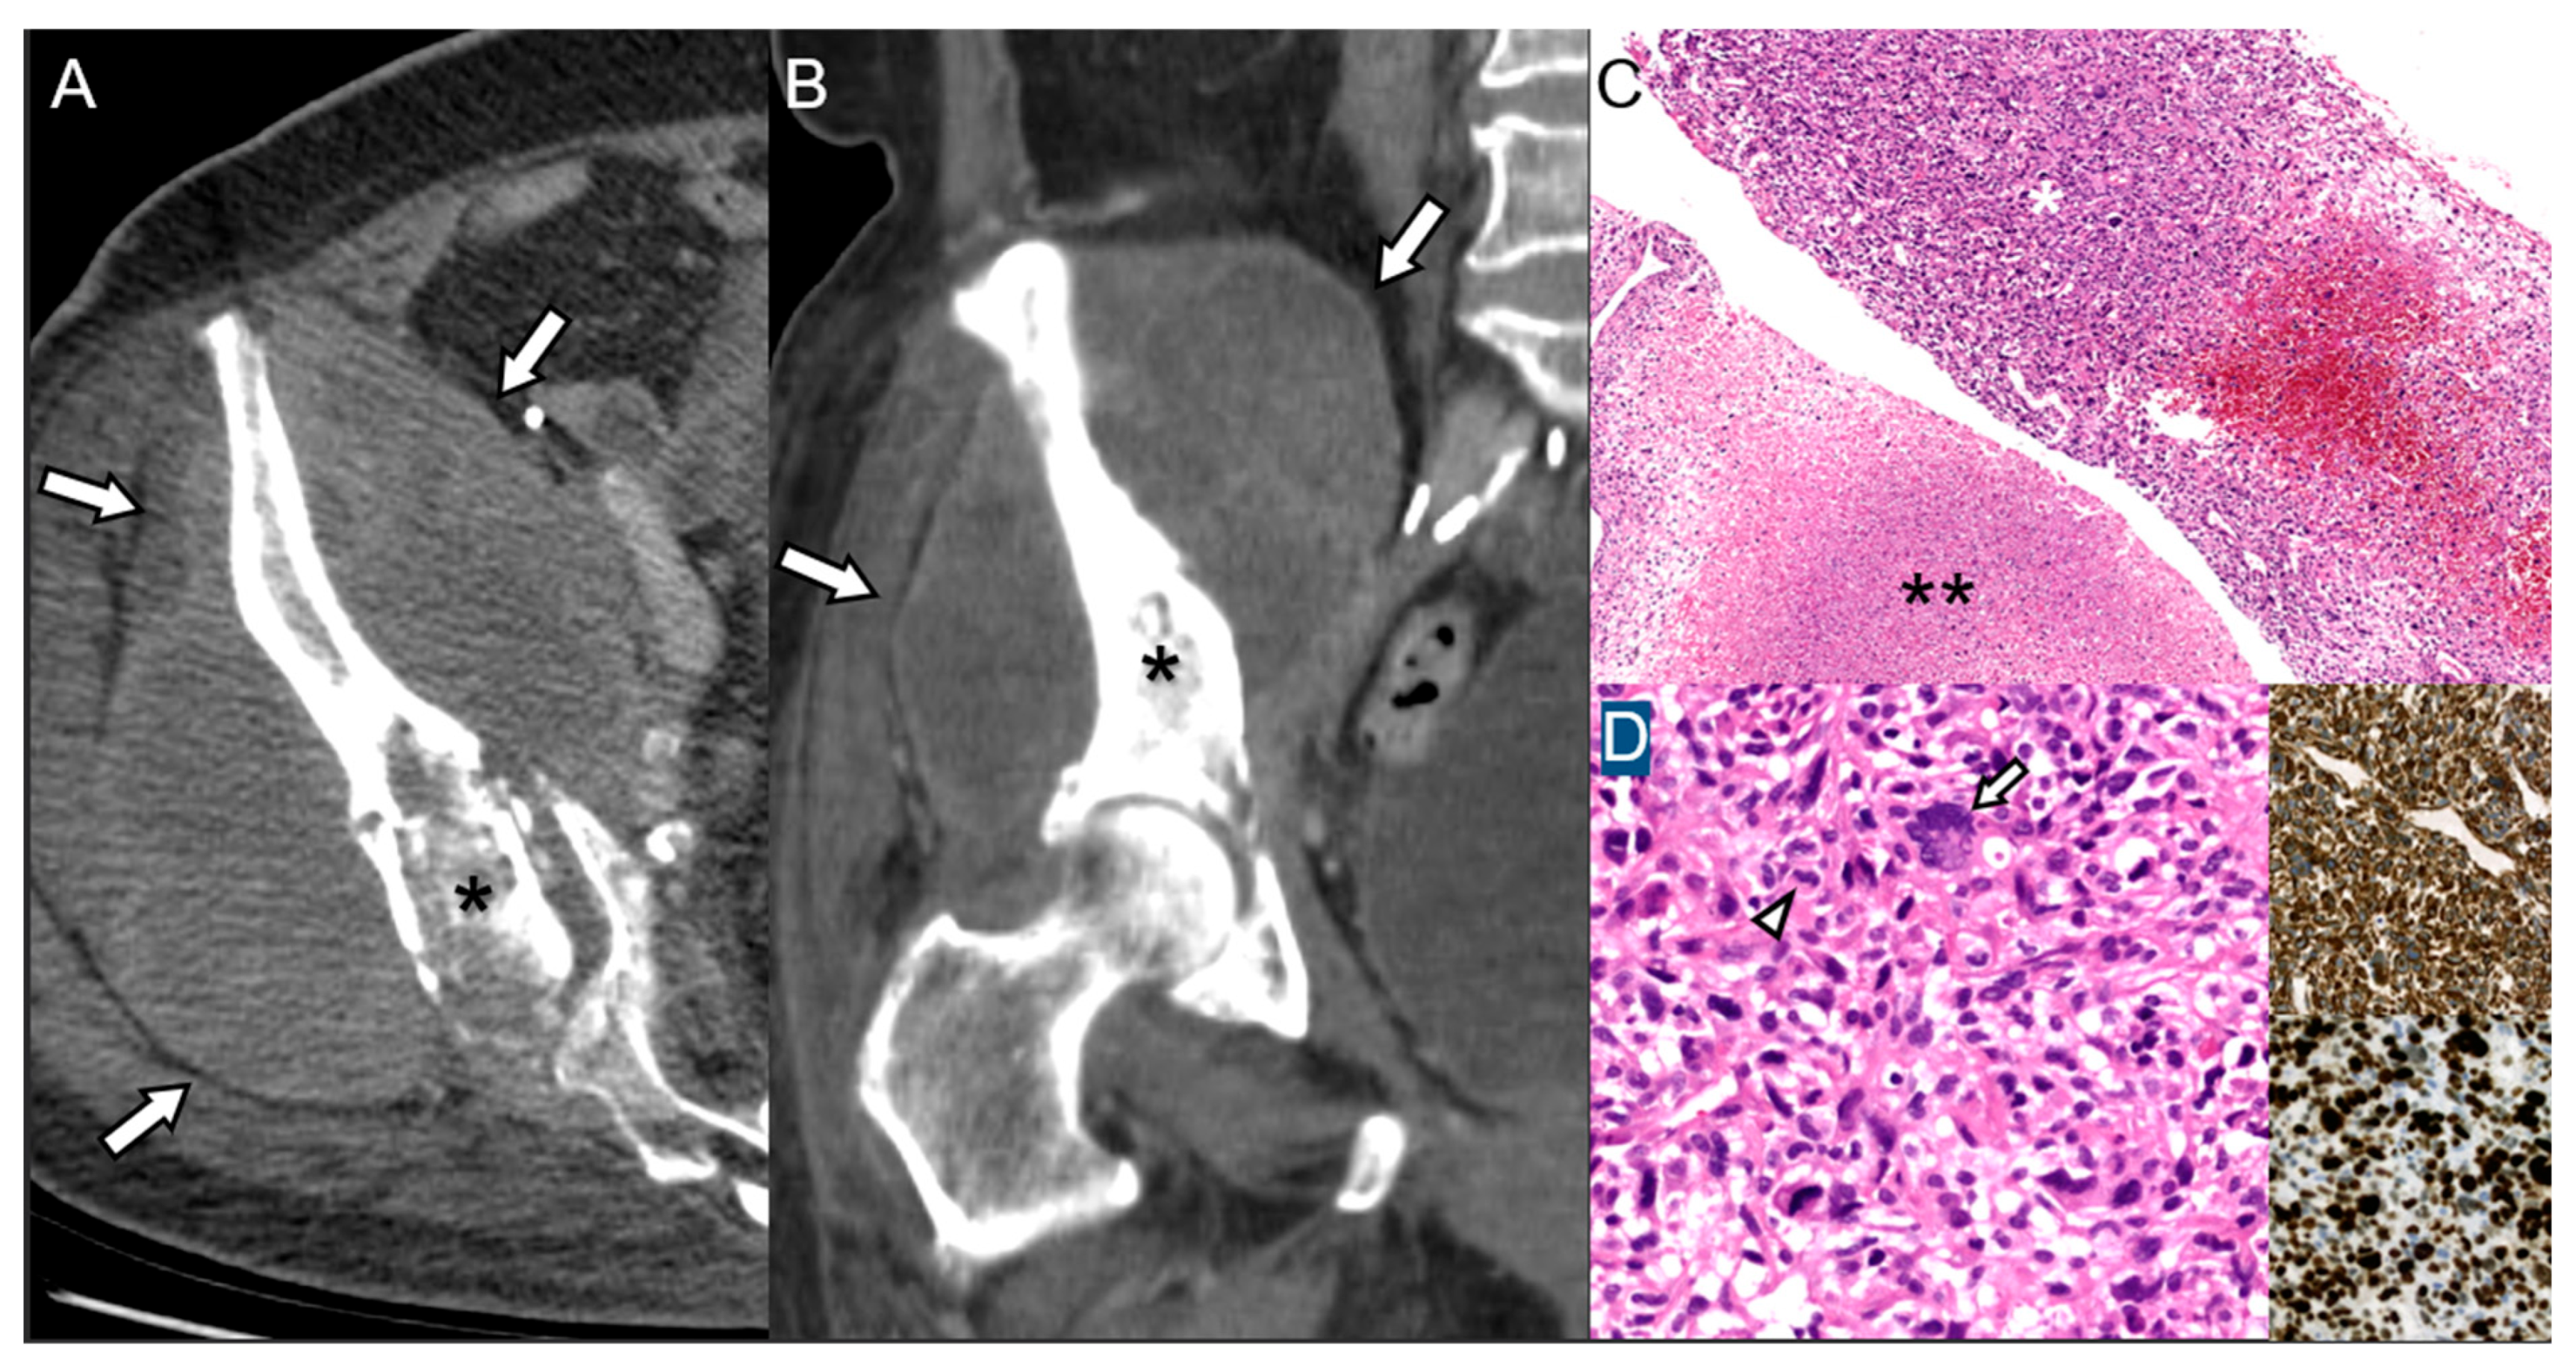

3.3. Bone Infarction